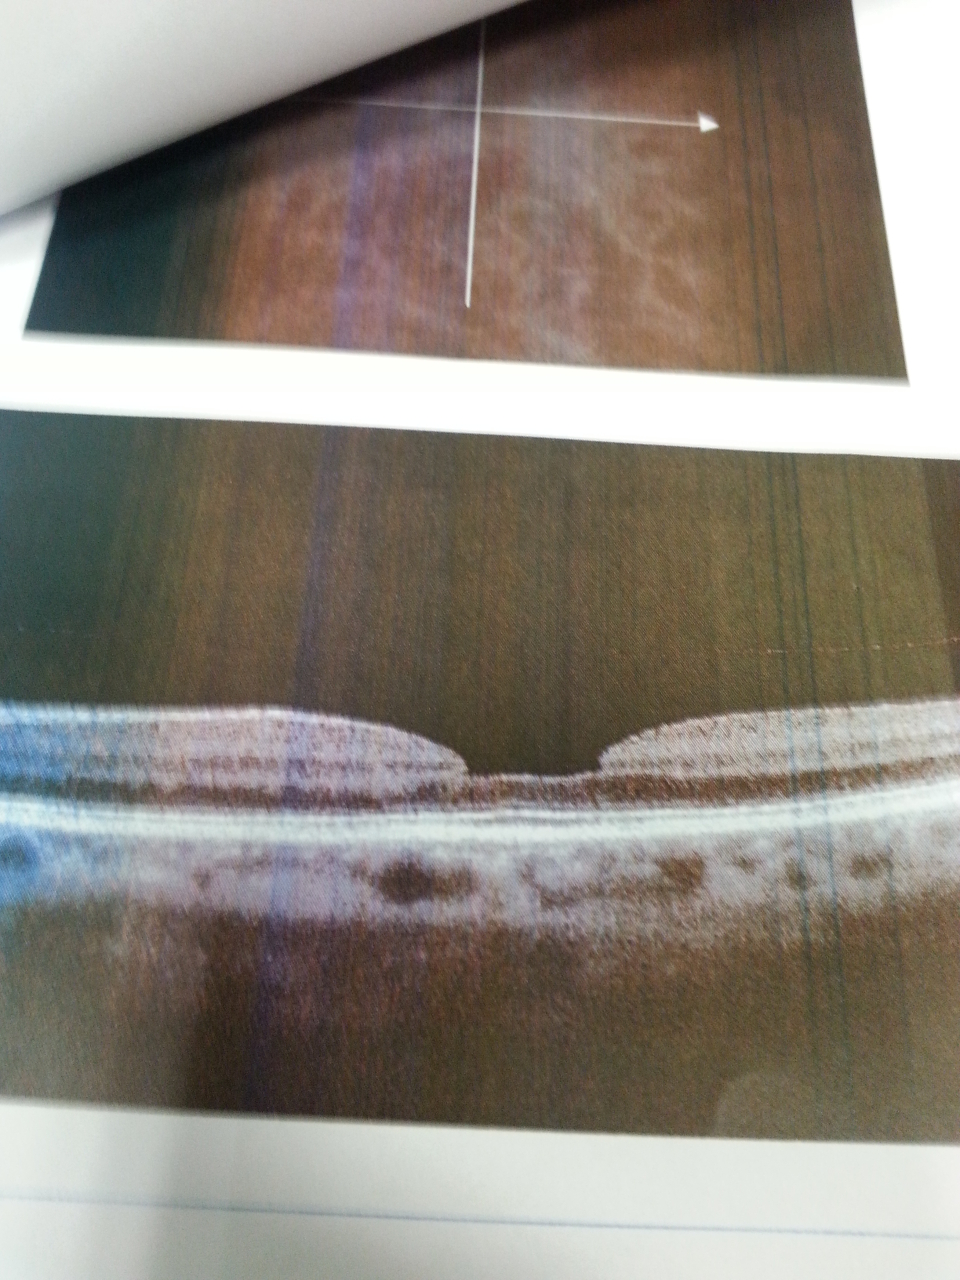

Paziente di 38 anni viene per mancato rinnovo patente causa ipovisus quadro clinico visus occhio destro 3/10 visus occhio sinistro 3-4/10 non migliorabili con lenti fundus: epiteliopatia retinica maculare con sospetto distacco sieroso

Effettuati OCT e Fluorangiografia (vedi allegati) che confermano la diagnosi

Paziente di 74 anni visto per pregressa occlusione venosa retinica con maculopatia edematosa già trattato con anti VEGF intravitreale. Il quadro clinico era il seguente: visus occhio destro 2/10 sf +2 fundus: maculopatia edematosa OCT e FAG: maculopatia edematosa (vedi foto).

Effettuato Ozurdex intravitreale, nel febbraio 2012 l’edema maculare è regredito completamente (vedi OCT), il visus si è portato dopo circa un mese a 6-7/10 sf +1 e attualmente novembre 2012 è 10/10 stentati (4 lettere su 5) sf + 1.25.

• fod: (vedi oct) foro maculare già sottoposto a vitrectomia e peeling maculare;

• fos: (vedi oct) iniziale foro maculare lamellare.

Effettuato OCT (vedi allegato): nell'occhio sinistro si evidenzia un distacco sieroso maculare

Effettuato OCT (vedi allegato) viene confermato il pucker maculare nell'occhio destro In considerazione del visus elevato e dell'assenza di metamorfopsie si decide di tenere controllato il paziente con visite oculistiche e OCT.